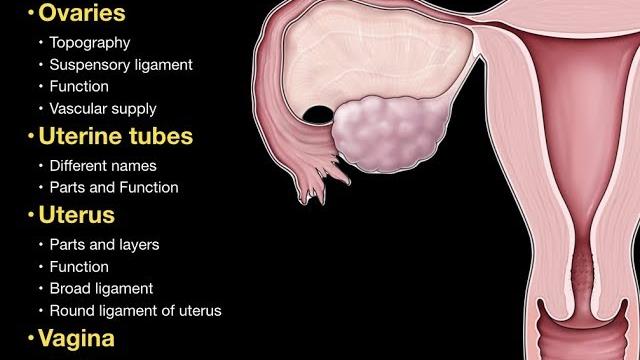

Girl pelvic

Для вашего запроса найдены видео: Guided meditation for pelvic floor relaxation | femfusion fitness, Best exercises for prolapse and bladder leaks safely strengthen your pelvic floor!, Clinical pelvimetry